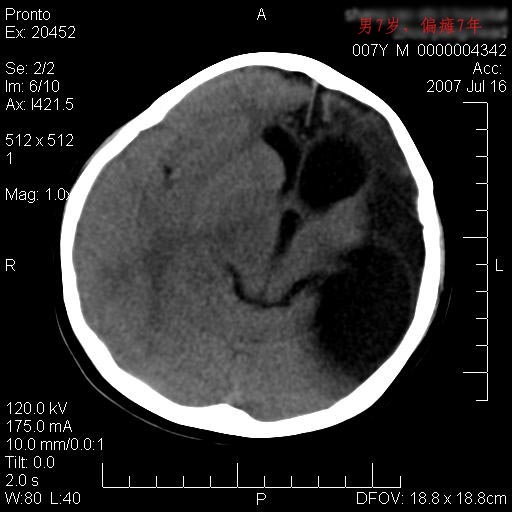

男性 7岁:偏瘫7年,出生时脑内出血。

左侧大脑半球发育不良、软化灶伴穿通畸形形成。

左侧脑叶体积缩小。密度减低,左侧脑室牵拉扩大并向左移位,左侧脑室颞角与侧裂池相通并呈囊性扩张。考虑左侧大脑发育不全,软化灶并穿通畸形。

左侧颅腔变小,左侧大脑半球体积缩小密度减低,呈负占位效应,左侧侧脑室扩大,出生时有脑出血病史。多考虑先天因素,左侧大脑前、中动脉起始部狭窄或闭塞,即烟雾病可能性大。